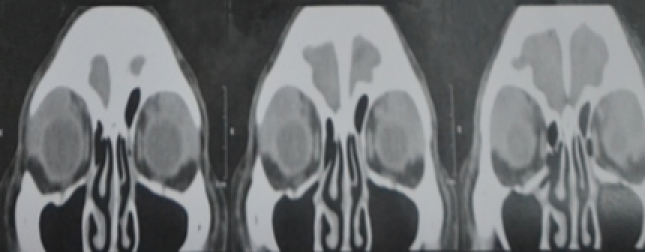

Our assessment at this point was an orbital lymphoproliferative disorder, bilateral; probably lymphoma with mechanical ptosis with good levator function, right upper eyelid; and suspicion of glaucoma in both eyes. To support our assessment, we needed imaging studies, which had fortunately already been ordered previously by the glaucoma specialist. On plain CT scan, we noted a homogenous mass with molding or contouring around the orbital structures.

On coronal view, we noted homogenous masses that mold around the globe and recti, and this also confirmed on axial cuts. This not only supported our assessment, it also effectively ruled out the other 3 differential diagnoses we had earlier (Figure 2 [Fig. 2], Figure 3 [Fig. 3]).

Figure 2: A coronal view of a plain orbital CT scan of the patient showing a homogenous mass molding around the globe and recti bilaterally

Figure 3: An axial view of a plain orbital CT scan of the patient showing a homogenous mass molding around the globe and recti bilaterally

Molding around orbital structures is the radiologic hallmark of orbital lymphoproliferative disorders, but it will not differentiate between benign and malignant disease. Consequently, our assessment was maintained.